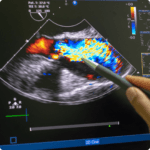

A veces, las señales son claras: un dolor agudo tras un mal paso, una sobrecarga en el gemelo tras ese último sprint o ese pinchazo en el tendón que lleva días avisándote de que algo no va bien. Pero otras veces, el problema no es tan evidente, y necesitas saber con exactitud qué ocurre para actuar cuanto antes. En esos momentos, nuestra ecografía muscular y tendinosa es tu mejor aliada. Nos permite ver con detalle qué está ocurriendo en tus músculos y tendones sin complicaciones, sin radiaciones y con resultados al instante.

Cuando hablamos de lesiones musculares y tendinosas, el diagnóstico rápido y preciso es clave para una recuperación eficaz. En AGM Fisioterapia no perdemos ni un minuto:

ver en vez de imaginar

Beneficios de usar la ecografía muscular y tendinosa

Diagnósticos en tiempo real:

Localizamos la lesión mientras tú nos cuentas tus síntomas.

Tratamientos más rápidos:

Saber exactamente qué ocurre nos permite actuar sin rodeos.

Seguimiento dinámico:

Adaptamos tu recuperación en cada fase según los resultados.

Personalización total:

Cada músculo y tendón tiene su historia, y cada tratamiento también.